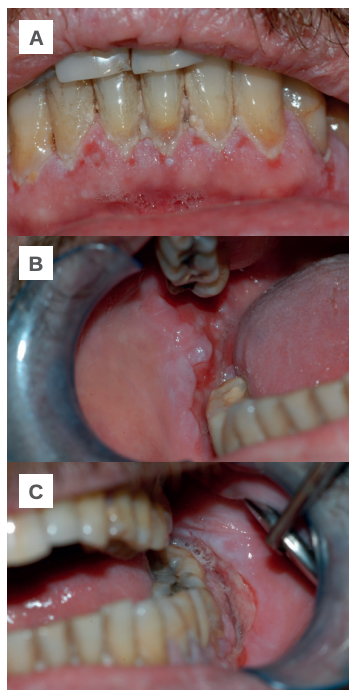

Tras la exploración intraoral se confirma que la mayor parte de las lesiones se localizan en el tejido gingival de la región antero-inferior, en mucosa yugal a nivel de los molares inferiores y en el fondo vestibular (Figuras 1-A, B y C). A la espera de un diagnóstico definitivo se le prescribe acetónido de triamcinolona 0,1%, con el que mejora en los tres días siguientes. Tras una nueva reagudización se intensifica el tratamiento corticoide suministrando dexametasona 4 mg inyectable (1 día/3 días) y 4 mg vía oral (1 día/5 días), con el que obtiene una notable mejoría durante las dos semanas siguientes.

A: región antero inferior. B: mucosa yugal derecha y fondo de vestíbulo. C: mucosa yugal izquierda y fondo de vestíbulo.

A nivel clínico la lesión primaria del PV es la ampolla, el resto de lesiones coalescentes (costras, erosiones y restos epiteliales) son el resultado de su evolución natural18. La ampolla suele presentar dimensiones variables, el contenido puede ser seroso, purulento o hemorrágico y puede asociarse a ampollas limítrofes con la sucesiva formación de placas erosivo-costrosas. En más del 50% de los casos el debut se localiza en la mucosa oral; según el área bucal interesada es posible encontrar erosiones irregulares, grandes y en ocasiones recubiertas por lesiones blanquecinas en la mucosa yugal; erosiones, costras y restos epidérmicos en labios; erosiones en el tejido gingival alrededor de los dientes; erosiones aisladas o coalescentes en paladar y erosiones especialmente dolorosas en la lengua19. En el PV cutáneo suelen localizarse en tronco, ingles, axilas, cuero cabelludo y cara20. Las lesiones observadas en este paciente afectaron a la mucosa yugal y a la encía del sector antero-inferior, constituyendo un límite importante para llevar a cabo una higiene oral adecuada y con la consecuente acumulación de placa en las caras vestibulares de sus dientes. No se registraron manifestaciones en el paladar, lengua o labios.